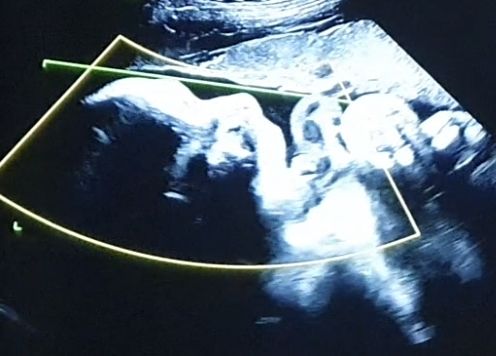

3 скрининг (32 недели и 4 дня)

Беременность 3 триместр

В полости матки визуализируется один живой плод в головном предлежании

Частота сердечных сокращений, ударов/минуту 146